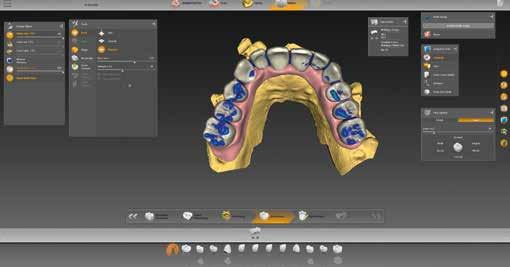

A tényleges munkát megelőzte a restauráció típusának kiválasztása. Kipipáltuk a multilayer és gingiva szavakat (6. ábra). Ezenfelül három hidat (14-16, 13-23, 24-26 régió) jelöltünk be, amelyek később a tercier részek lesznek. A „Modell” munkafázisban külön-külön megnézhettük a maxilla és mandibula mintáját (7. ábra), és ellenőrizhettük az intermaxilláris távolságot (8. ábra). A BioCopy alapján pontosan állíthattuk be a két mintát egymáshoz képest (9. ábra). Ezt követte egy nagyon fontos lépés: a felső állcsont gerinc-középvonalának berajzolása (10.

9. ábra: A BioCopy szkennelés alapján illesztjük a felső és alsó mintát. 6. ábra: Az adminisztratív fázisban meghatározzuk az alapbeállításokat, aktiváljuk a „multilayer” és „gingiva” mezőket.

11–12. ábrák: Az adhezív sapkák szélének meghatározása – lehet manuális vagy automatikus is.

ábra). A képernyő jobb oldalán megfigyelhető. Berajzoltuk az adhezív sapkák széleit (11–12. ábrák), ez automatikusan, vagy kézzel is történhet. Végül meghatároztuk a behelyezési irányt. A tervezés során meg kellett adnunk alapvető paramétereket, például a vastagságot illetően (13. ábra). A kívánt anatómiai formát számos lehetőség közül választhatjuk ki a könyvtárból (14. ábra). Az eddig beolvasott adatok és a terv paraméterei alapján a szoftver javasol egy megoldási variációt, három híddal és gingivarésszel (15–21. ábrák). Ez a továbbiakban egyedileg módosítható, mielőtt az inLab CAM szoftverbe küldjük (22–26. ábrák).